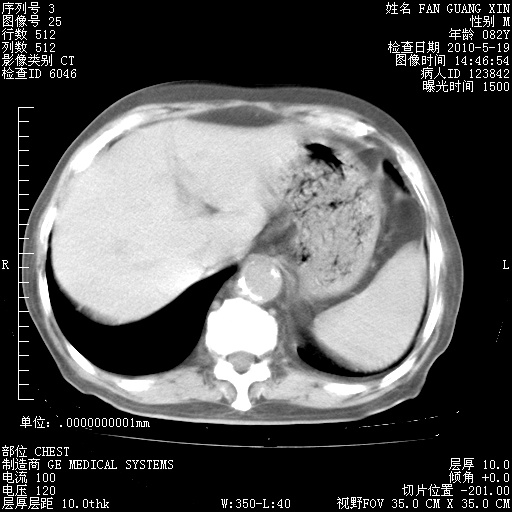

再治疗10天后的肺部CT

再治疗10天后的肺部CT 纵膈窗

阅读此次胸部CT,肺间质渗出性改变较入院时有吸收。目前从体温、白细胞、中性分叶明显增高,肯定存在细菌感染(发生医院感染哦,若无消化道及泌尿系统等感染的依据,肺部感染可能大)。若你院头孢哌酮舒巴坦钠耐药率较高,同意你的方案,若48小时体温仍高,可考虑使用碳青霉稀类抗菌药物,同时可予超声雾化、注意滴数时加大液体量。白蛋白33.30g/L较低哦,需加强营养等支持治疗。